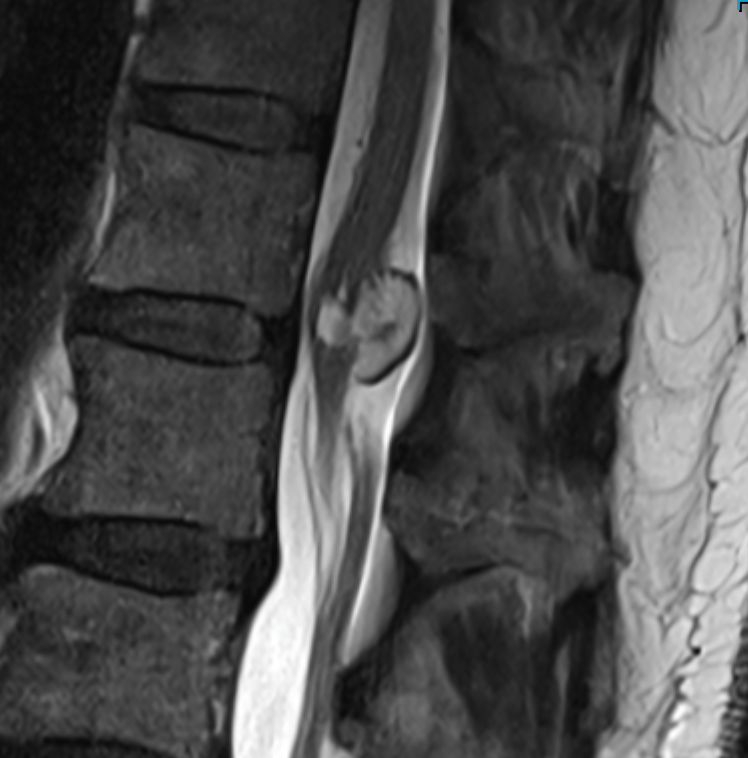

A sagittal MRI scan of the lower spine showing the spinal cord extending lower than normal, attached to a mass.